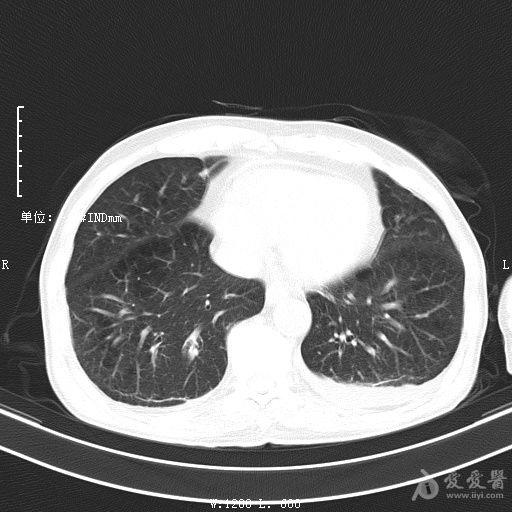

最新的肺炎疫情形勢嚴(yán)峻,病毒變異使得防控工作更加復(fù)雜,許多地方出現(xiàn)了新的病例,甚至有些地區(qū)的疫情出現(xiàn)了反彈,這不僅是對(duì)醫(yī)療系統(tǒng)的考驗(yàn),更是對(duì)每一個(gè)生命的考驗(yàn),我們需要密切關(guān)注疫情動(dòng)態(tài),共同應(yīng)對(duì)這場挑戰(zhàn)。??